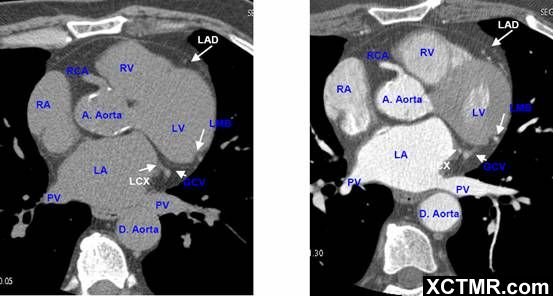

常用英文名称及缩写 LA - Left Atrium 左心房 RA - Right Atrium 右心房 LV - Left Ventricle 左心室 RV - Right Ventricle 右心室 Mitral Valve 二尖瓣 A. Aorta-Ascending Aorta 升主动脉 D. Aorta-Descending Aorta 降主动脉 SVC – Superior Vena Cava 上腔静脉 IVC – Inferior Vena Cava 下腔静脉 PA - Pulmonary Artery 肺动脉 PV - Pulmonary Vein 肺静脉 LMA - Left Main Artery 冠状动脉左主干 LAD - Left Anterior Descending Artery 左前降支 LCX - Left Circumflex Artery 左回旋支 LMB - Left Obtuse Marginal Branch 左边缘支(钝缘支) RCA - Right Coronary Artery 右冠状动脉 PDA - Posterior Descending Artery 后降支 Conus Branch 右动脉圆锥支 LAA – Left Atrial Appendage 左心耳 RAA – Right Atrial Appendage 右心耳 CS - Coronary Sinus 冠状窦 MCV – Middle Cardiac Vein 心中静脉 GCV –Great Cardiac Vein 心大静脉 PIVV – Posterior Intraventricular Vein 后室间静脉(心中静脉) PLVV – Posterior Left Ventricular Vein 左室后静脉 PLV – Posterior Lateral Vein 左室后侧静脉(边缘静脉) | |